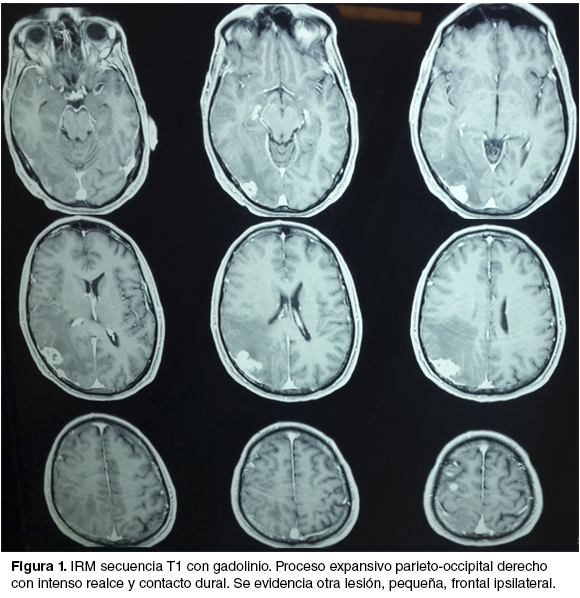

Historia de 3 meses de evolución de cefalea progresiva y déficit motor leve de hemicuerpo izquierdo, que retrocede con la corticoterapia. Se realizó imagen por resonancia magnética (IRM) que evidencia una lesión expansiva parieto-occipital derecha con contacto dural y otra más pequeña frontal ipsilateral (figura 1). Con planteo de secundarismo encefálico se realiza cirugía electiva de la lesión parieto-occipital. Se reseca la misma en bloque junto con la duramadre infiltrada y se realiza una plastia de duramadre con periostio. Durante la mayor parte del acto anestésico-quirúrgico el paciente se mantiene hipertenso, con cifras mayores a 160/90 mmHg. Se realiza hemostasis con PA de 170/100 mmHg, momento en el cual el paciente instala una arritmia y un infradesnivel del segmento ST, que revierten rápidamente.